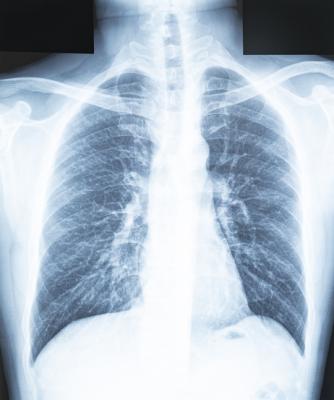

Getty Images

September 26, 2023 — In a study of more than 2,000 chest X-rays, radiologists outperformed AI in accurately identifying the presence and absence of three common lung diseases, according to a study published in Radiology, a journal of the Radiological Society of North America (RSNA).

The chest X-rays were assessed for three common findings: airspace disease (a chest X-ray pattern, for example, caused by pneumonia or lung edema), pneumothorax (collapsed lung) and pleural effusion (a buildup of water around the lungs).